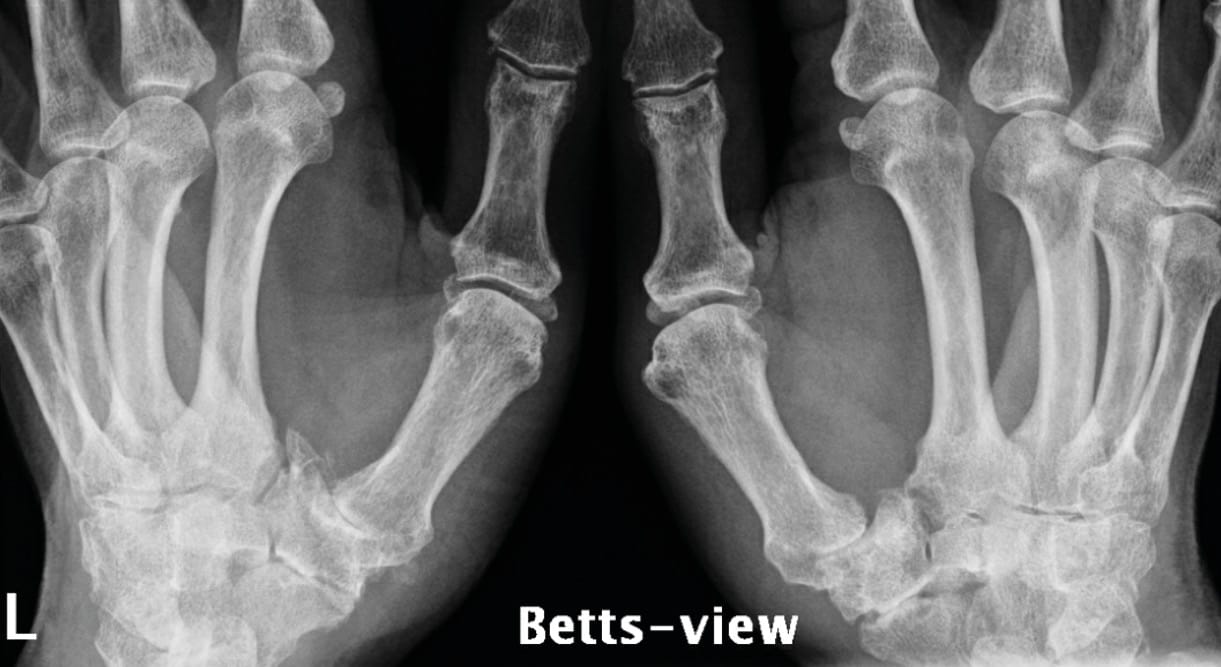

Finally, we must not overlook visualisation all of the peritrapezial joints, better known as the view described by Gedda [9] Kapandji AI, Moatti E, Raab C. La radiographie spécifique de l’articulation trapézo-métacarpienne. Sa technique, son intérêt. Ann Chir Main 1980;34:719-26. and popularised by Taleisnik as Bett’s view [10] Kapandji TG, Kapandji AI. Nouvelles données radiologique sur la trapézo-métacarpienne. Résultats sur 330 dossiers. Ann Chir Main 1993, 12 , N°4, 263-274, which frees up the trapezium perimeter to offer very good visualisation of the whole area (Figure 7). To obtain good quality visualisation of the triscaphoid joint it is useful to take frontal views in ulnar and radial deviation. Some triscaphoid joints appear ‘normal’ on imaging at rest and collapse completely in radial deviation (Figure 8).

Radiological assessment of painful basal thumb arthritis will consist of Kapandji’s frontal and lateral views, an Eaton frontal view (which can replace Kapandji’s frontal view if necessary) and stress view of the TMC, a dynamic triscaphoid view and a Gedda's (Bett’s) view [12], Gedda KO (1954). Studies on Bennett’s fracture: anatomy, roentgenology and therapy. Acta Chirurgica Scandinavica, 193(Suppl): 1. [13] Taleisnik J. The Wrist, 1st edn. New York, Churchill Livingstone, 1985: 95–96. (Figure 9).